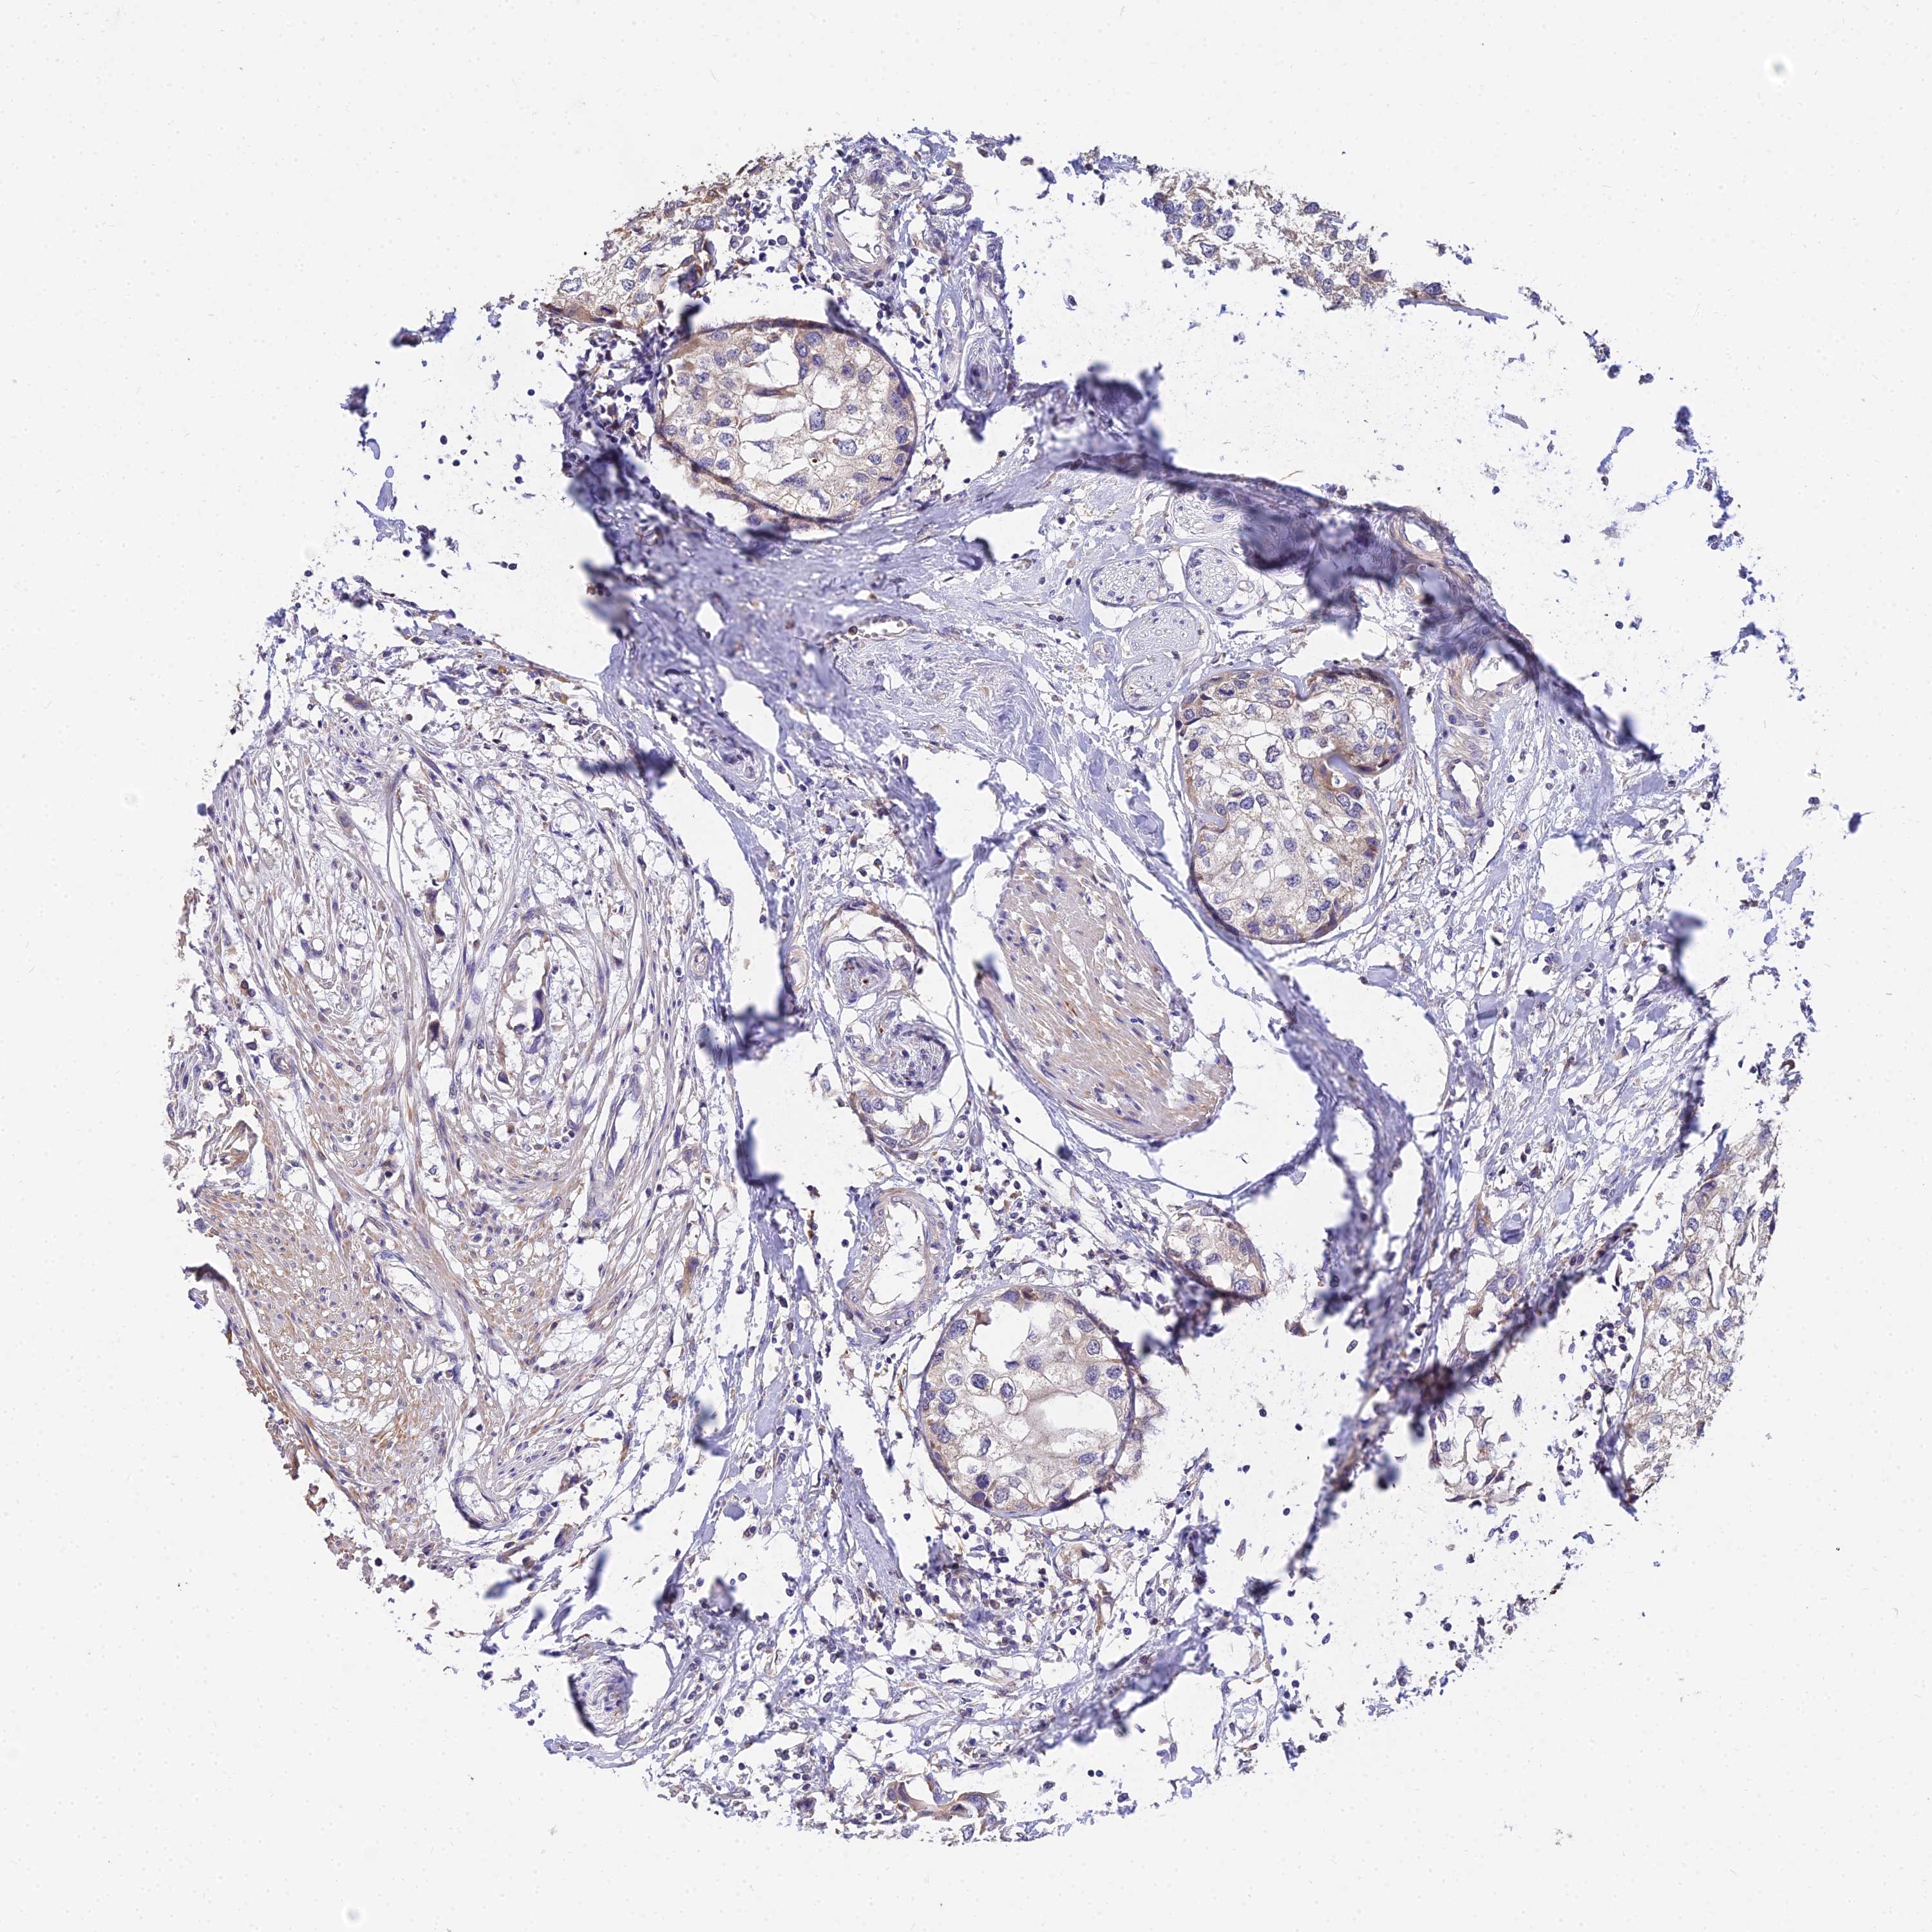

UROTHELIAL CANCER - Protein expressioni

A mouse-over function shows sample information and annotation data. Click on an image to view it in a full screen mode. Samples can be filtered based on level of antibody staining by selecting one or several of the following categories: high, medium, low and not detected. The assay and annotation is described here.

Note that samples used for immunohistochemistry by the Human Protein Atlas do not correspond to samples in the TCGA dataset.

Antibody stainingi

Antibody staining in the annotated cell types in the current human tissue is reported as not detected, low, medium, or high, based on conventional immunohistochemistry profiling in selected tissues. This score is based on the combination of the staining intensity and fraction of stained cells.

Each image is clickable and will lead to virtual microscopy that enables deeper exploration of all samples and also displays staining intensity scores, fraction scores and subcellular localization as well as patient and tissue information for each sample.

Antibody HPA038759

Antibody HPA040515

Antibody HPA045924

Urothelial carcinoma, High grade

Urothelial carcinoma, Low grade